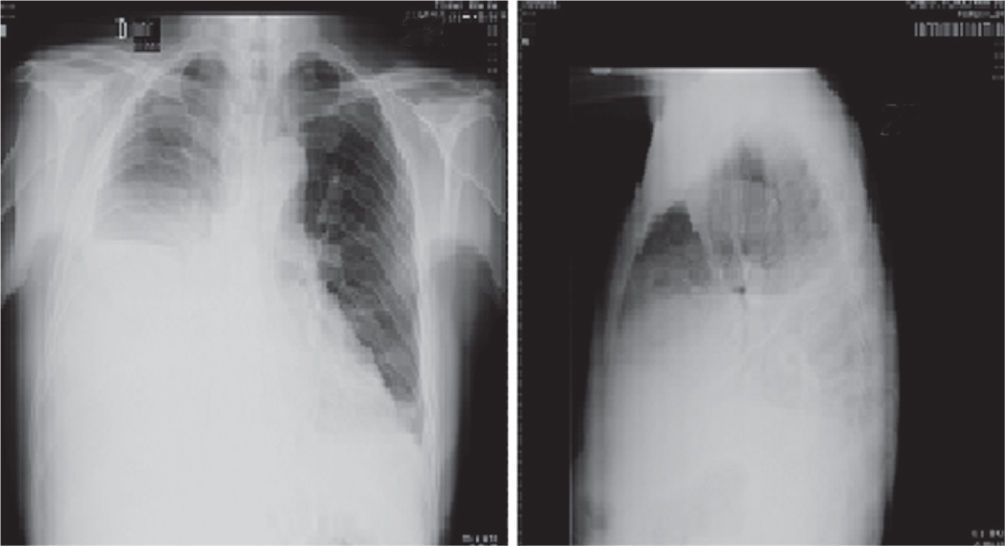

Presentación de casoPaciente masculino en la octava década de la vida, 72 años, de ocupación agricultor, quien ingresa al servicio de urgencias por presentar cuadro clínico de un mes de evolución, consistente en dolor de aparición progresiva en hemitórax derecho que se exacerba durante la inspiración y se irradia a horquilla esternal, asociado a disnea progresiva de pequeños a medianos esfuerzos, odinofagia. Cuatro días previos al ingreso presenta exacerbación de los síntomas, asociado a lesión eritematosa y descamativa en la cara (fig. 1A) y en la zona de exposición solar en tórax (fig. 1B) además de edema periorbitario en manos y miembros inferiores. Como antecedentes de importancia refiere exposición prolongada al humo de leña. Como hallazgos positivos al examen físico presentaba inyección conjuntival, edema periorbitario, mucosa oral seca con úlceras de fondo limpio, expansibilidad del tórax asimétrico, con movimientos respiratorios disminuidos en hemitórax derecho, así como ruidos respiratorios velados de forma ipsilateral, ruidos cardiacos taquicárdicos de intensidad disminuida y edema grado II con fóvea en miembros inferiores. En la química sanguínea se evidenció leucopenia y proteína C reactiva (PCR) elevada. Posteriormente, se realizó ecocardiograma transtorácico que reportó fracción de eyección del ventrículo izquierdo conservada y radiografía de tórax (figs. 2A y 2B) que documentó derrame pleural masivo en hemitórax derecho con desviación de la tráquea ipsilateral. Se realizó toracentesis diagnóstica y evacuatoria que demostró exudado linfocítico; los estudios para mycobacterias (reacción en cadena de polimerasa y cultivo) fueron negativos; así mismo se realizó estudio imaginológico con escanografía de tórax con el fin de descartar etiología neoplásica (fig. 3), además de bloque celular y estudio citológico los cuales fueron negativos para neoplasia, en el TAC de tórax se confirmó la presencia de derrame pleural derecho y derrame pericárdico sin evidencia de lesiones de características tumorales. Dada la presencia de derrame pleural y hallazgos en piel, se consideró relevante descartar compromiso autoinmune tipo lupus eritematoso sistémico con actividad, por lo que se solicitaron estudios adicionales que reportaron ANAS y anti DNA positivos con complemento consumido (tabla 1). Debido a los hallazgos inmunológicos y cuadro clínico de poliserositis asociado a compromiso cutáneo, hematológico por leucopenia con linfopenia y eritema malar, ulceras orales, se consideró cuadro compatible con lupus eritematoso sistémico del anciano, por lo que se ampliaron estudios con base en detección de compromiso renal, el cual fue negativo. Se inició manejo inmunomodulador con esteroides con el cual el paciente presentó mejoría clínica y fue dado de alta.

Radiografías de tórax proyecciones PA y lateral, en las que se observa radioopacidad completa de los dos tercios inferiores del hemitórax derecho con borramiento del contorno diafragmático y cardiaco de este lado y desviación del cardiomediastino hacia la izquierda, por derrame pleural. Mala definición del ángulo costofrénico lateral izquierdo probablemente por escaso derrame pleural de este lado.